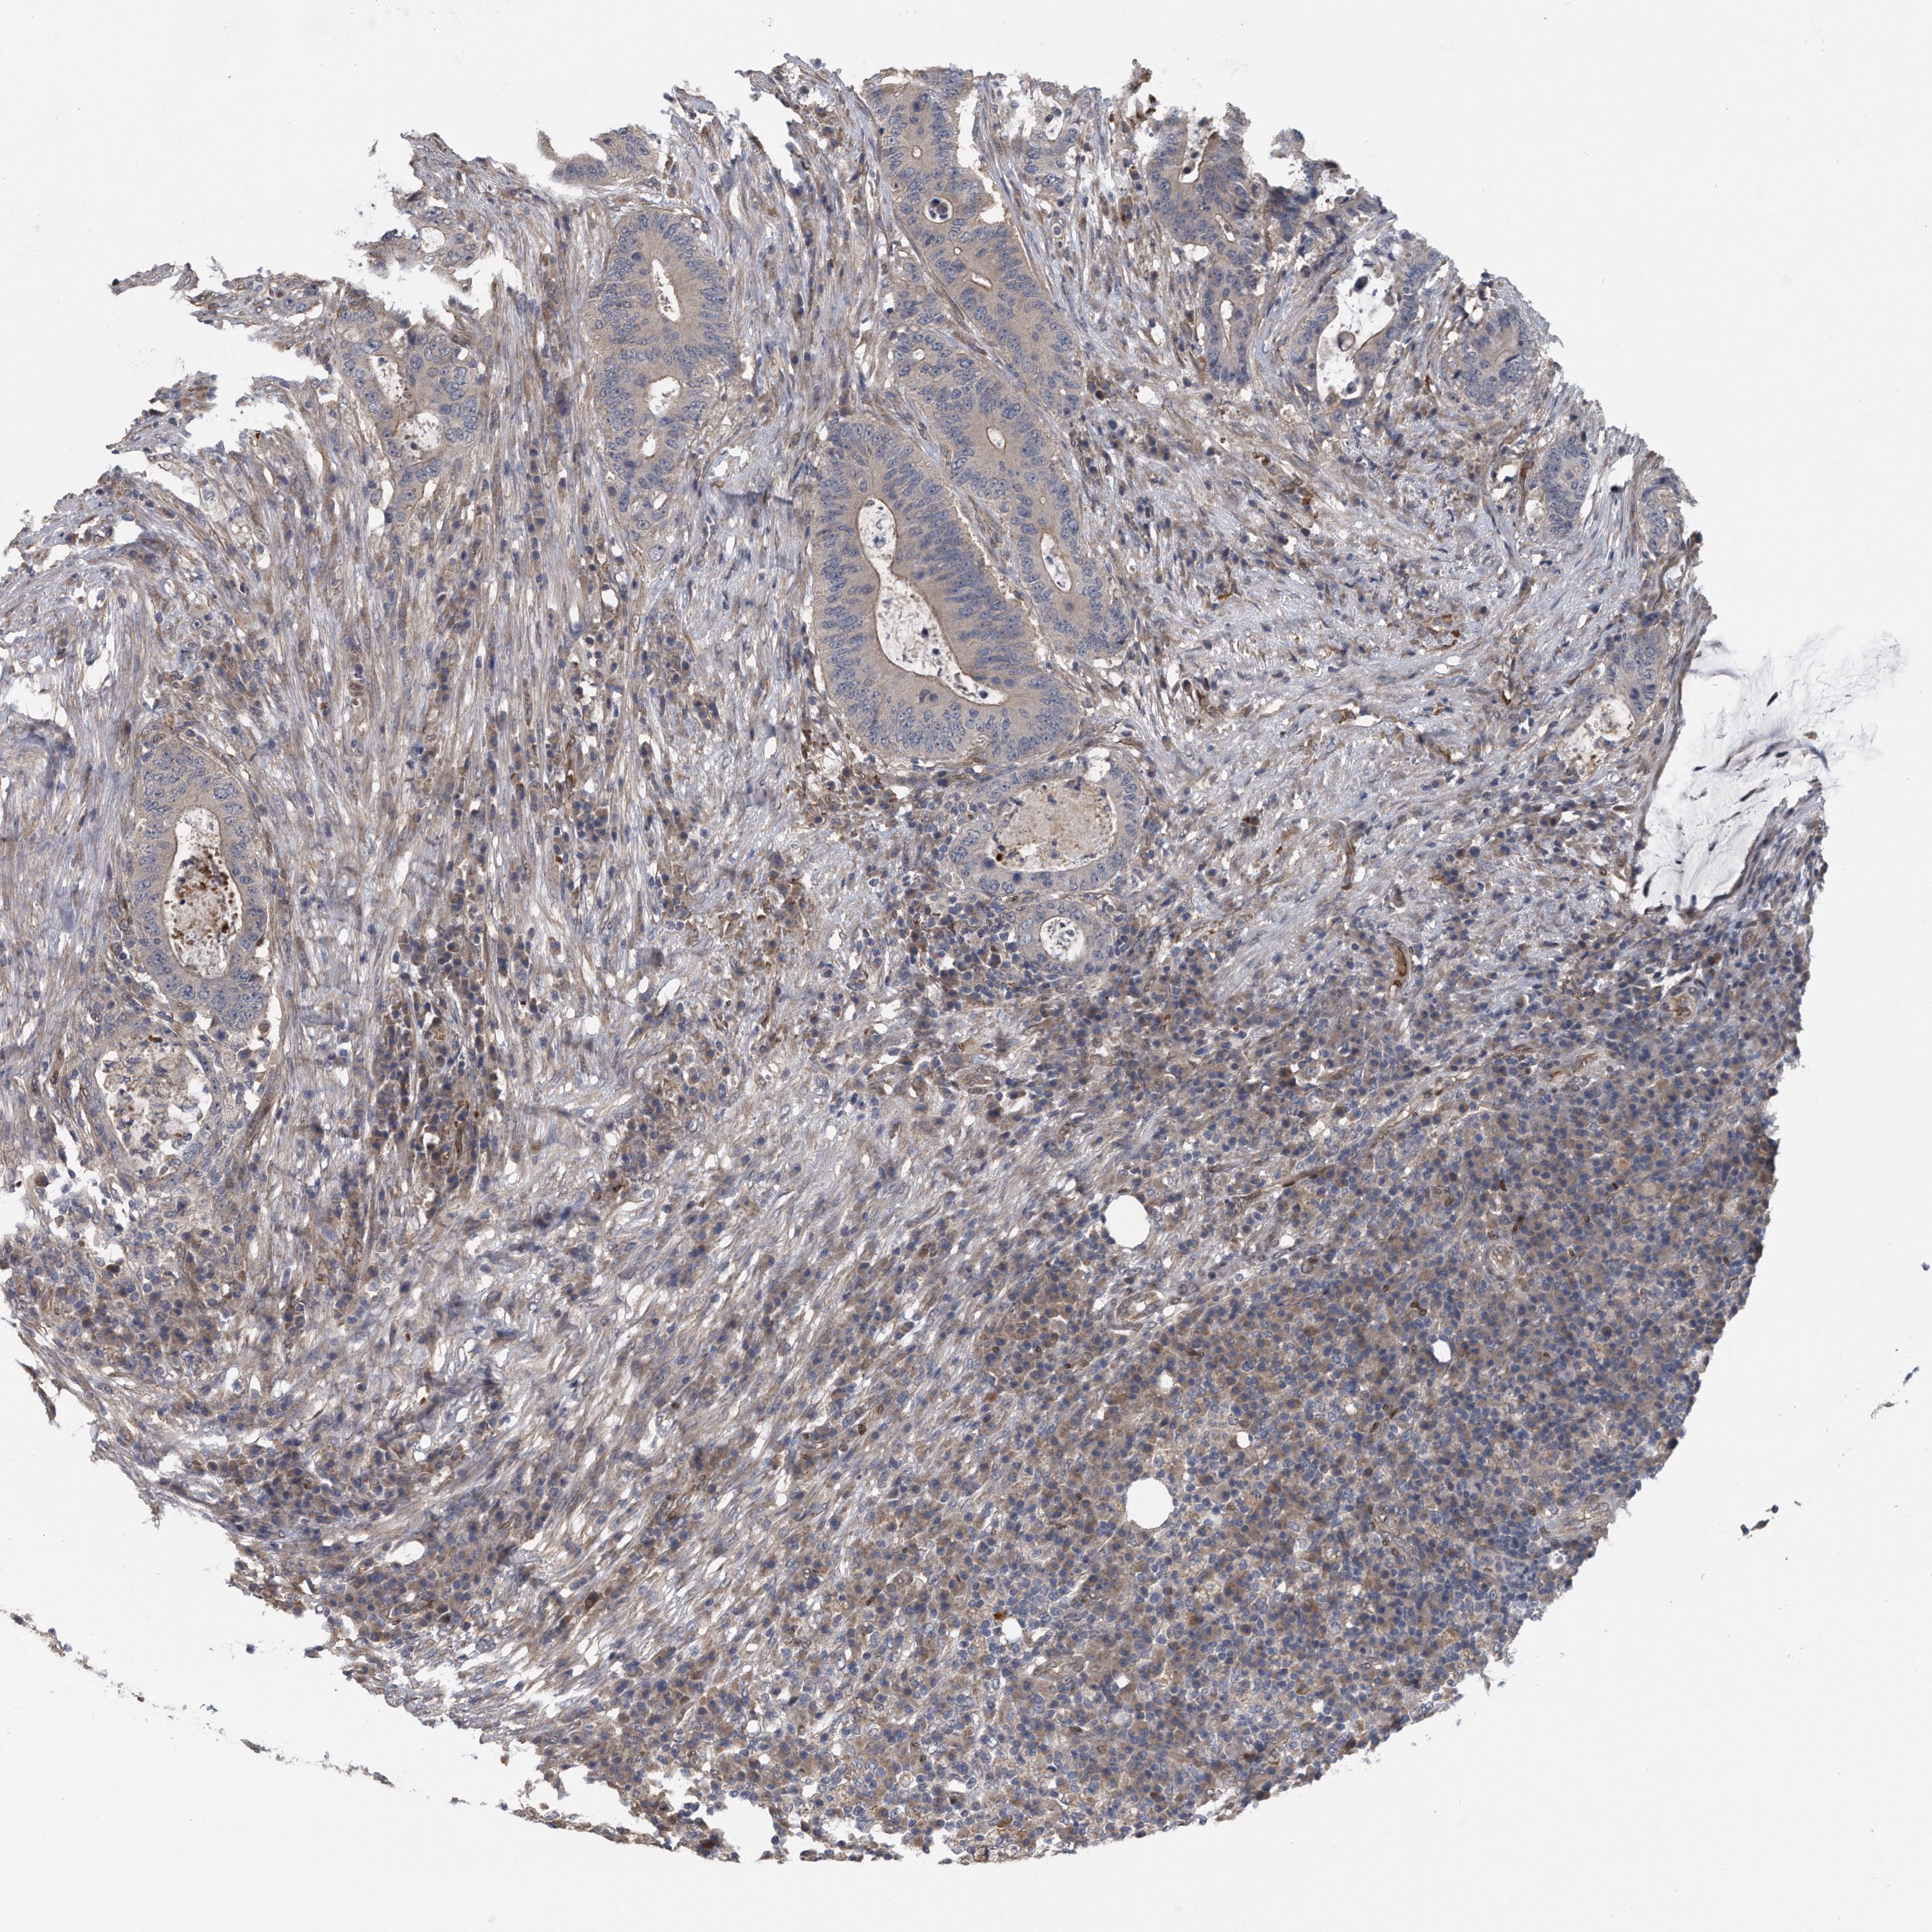

TCGA RNA samplesi

RNA-seq data is reported as average FPKM (number Fragments Per Kilobase of exon per Million reads), generated by the The Cancer Genome Atlas (TCGA) .

Normal distribution across the dataset is visualized with box plots, shown as median and 25th and 75th percentiles. Points are displayed as outliers if they are above or below 1.5 times the interquartile range. FPKM values of the individual samples are presented next to the box plot.

Average pTPM 8.7

Number of samples 207

Samples

Sample Description pTPM